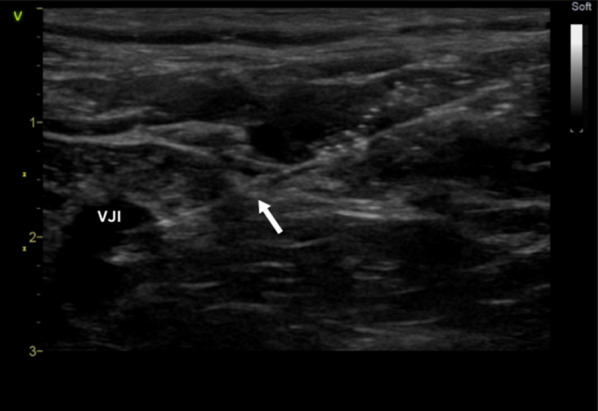

Results: A total of 200 subjects were equally divided between Group A and Group B. For the primary outcome, there was no significant difference in first attempt success rate (Group A: 79, Group B: 77, p = 0.434). Secondary outcomes, including complications and catheter functional time, did not differ significantly between the groups. However, the novel technique demonstrated a significantly faster procedure time (Group A: 315 s, Group B: 330 s, p = 0.016). Notably, the novel approach was linked with significantly larger IJV diameter measured during the procedure (Group A: 18.2 mm, Group B: 12.1 mm, p < 0.001).

Conclusion: The novel lateral in-plane short-axis approach for IJV cannulation is a non-inferior alternative with a lower incidence of posterior vessel wall puncture compared to the conventional approach.